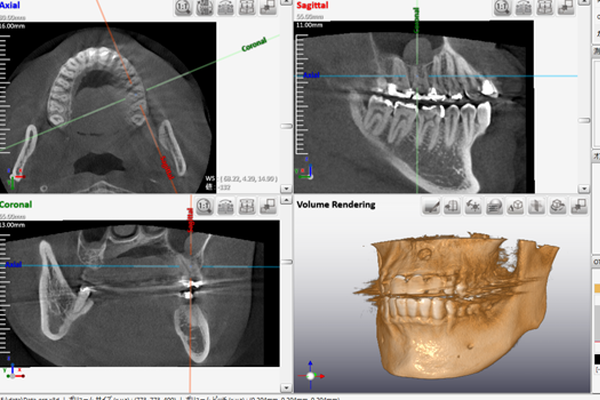

歯科用CTによる精密診断